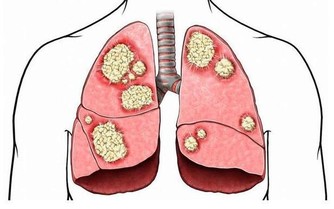

3、大魚大肉、愛喝酒吃太多蛋白類食物,會產生過多的尿酸和尿素氮等代謝廢物,加重腎臟負擔。

大量飲酒容易導致高尿酸血症,這些習慣可引起高血脂等代謝疾病,引發腎臟疾病。